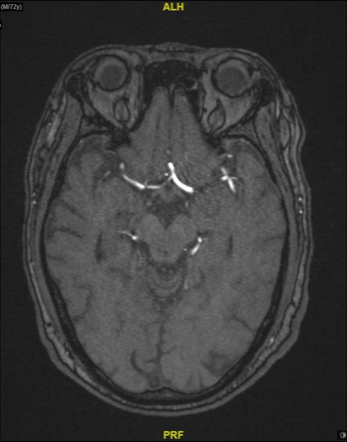

图4 TOF像显示岩骨段慢血流

图5 眼段可见正常管腔,血管负性重构

图6 M1段血管存在